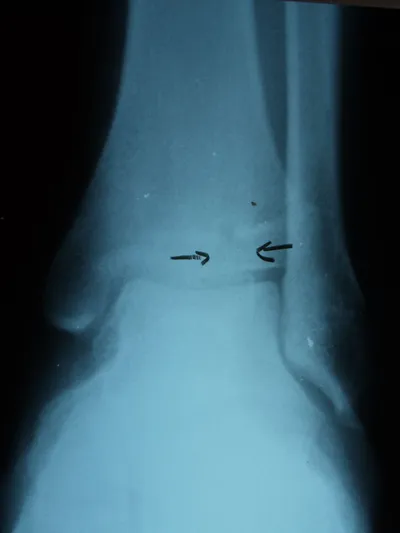

Salter III

The x-ray below shows a Salter III type injury to the tibia epiphysis indicated by the arrows.

Salter Harris III fractures begin at the joint surface of the epiphysis and progresses physis where it turns approximately 90 degrees and extends to the periphery.  Generally, these fractures occur in older children because the growth plates are nearing closure.  These fractures should be accurately be reduced if displaced.  Closure of the growth plate is of a concern due to damage to the growth plate blood vessels.